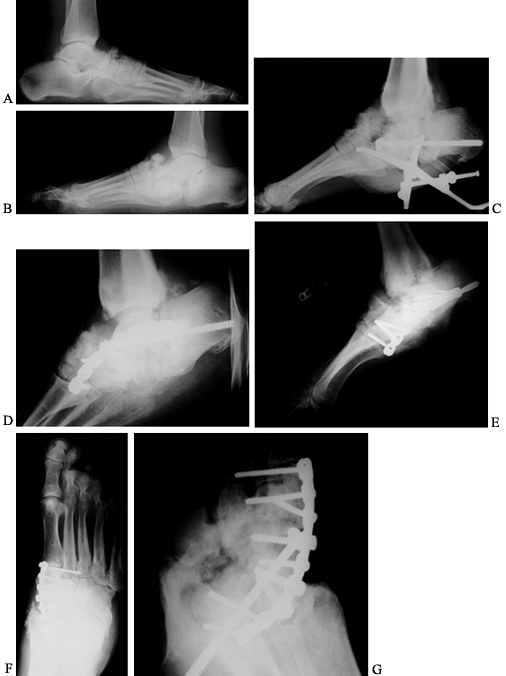

![]() |

Figure 116.7. A,B:

Black man, 55 years of age, who worked in hospital as a radiology technician. He had IDDM for 12 years before he noticed both feet swelling for 2 years before presentation. At presentation, he had minimal pain and was placed in extra-depth diabetic shoes for bilateral, midfoot, early Charcot’s joints. The condition continued to progress on the right side, so he underwent bilateral midfoot and hindfoot fusions 2 years later. Six years later, the deformities have stabilized (C–G) and the patient is disabled. |